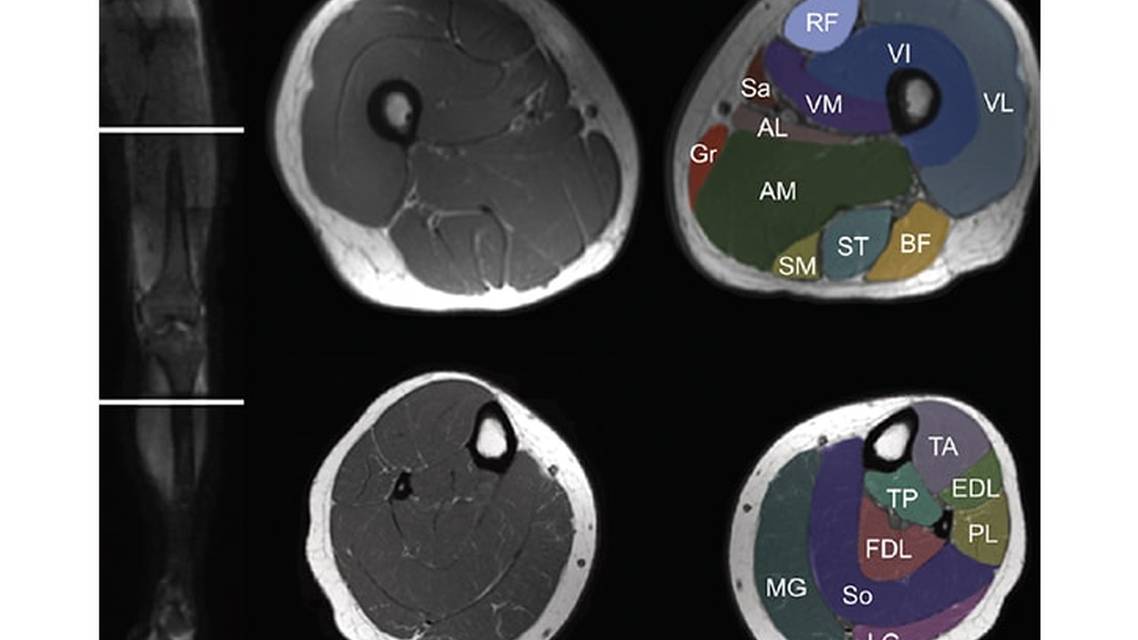

Most studies of muscle MRI have focused on the lower limbs, where the pattern of muscle involvement is usually established with 1 cross-section from the thigh and 1 cross-section from the lower leg (Figure 1). This is in part because the upper limbs are technically more challenging to image, but also because of the greater frequency of lower limb involvement in myopathies. Whole-body MRI would offer a more comprehensive evaluation with additional cross-sections from the upper limbs, axial, and sometimes cranial muscles.13